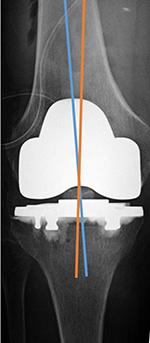

| Total Knee arthroplasty (TKA) Evaluation |

| 67 year-old woman. Postoperative images of a Biomet XPA Bicruciate Preserving TKA. Same patient as above. On the AP view (left image) the femorotibial angle is the intersection between the femoral anatomic axis (blue line) and the tibial anatomic axis (orange line). The femoral component should be centered along the femoral anatomic axis, and the tibial component should be perpendicular to the tibial anatomic axis. The femorotibilal angle should be 4-7° valgus. On the lateral view (right image) the femoral component should be roughly perpendicular to the femoral anatomic axis (orange line), and the tibial component should be perpendicular to the tibial anatomic axis (blue line) or have slight flexion (3°–6°) [posteriorly sloped]. |

Same patient as left two images. Another way to evaluate the TKA on the lateral view is to draw line C-D through anterior and posterior margins of the femoral component and line A-B perpendicular to line C-D. Line E-F is along the anatomic axis of the femur. The angle between lines A-B and E-F should approximate 30°. |